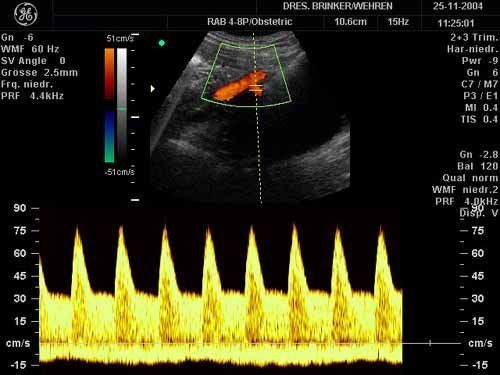

Farbcodierte Doppler-Ultraschallunterschung

Darstellung der Blutversorgung der Gebärmutter